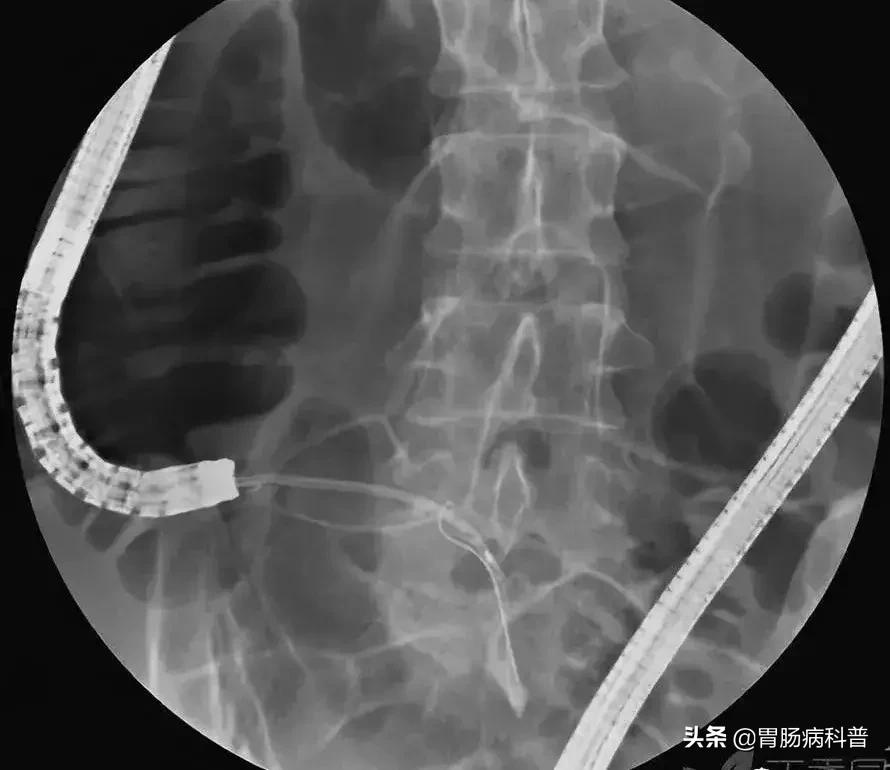

2.内镜逆行性阑尾造影术(endoscopic retrograde appendicography,ERA):

X线下,阑尾腔内注入造影剂显示阑尾腔的形态(椭圆形线圈),如有粪石(黑箭头),则行球囊取石术。并确认有无阑尾穿孔。

4.塑料支架置入及脓液引流:

在充分取出粪石后,置入塑料支架行脓液引流及进一步阑尾腔冲洗(生理盐水+抗生素)。

X线下查看阑尾腔内支架的位置及形态:

放置的支架于术后一周左右肠镜下取出。